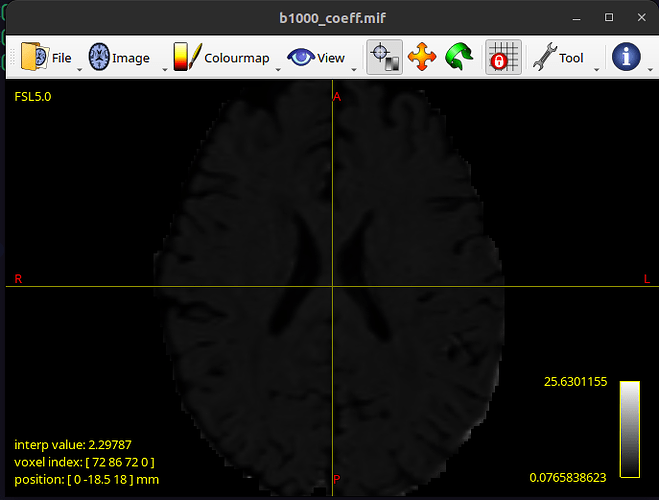

and as a result b1000_coeff.mif looks like this: